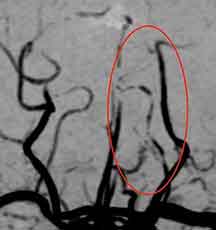

頭部MRA検査では、

椎骨動脈という、首から後頭部へ行く血管が変形しており、椎骨動脈解離と診断しました。